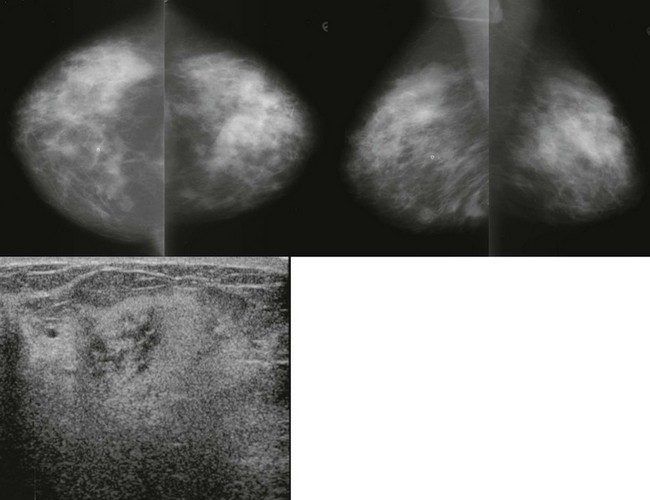

Rhabdomysarcoma and leukemic infiltrates can present as palpable thickening with asymmetry on mammography and poorly defined areas of hyperechogenic breast tissue on US (Fig. 11-20). Fat necrosis differs in appearance; it is typically subcutaneous and better defined.

FIGURE 11-20 Leukemia of the Breast.

A 28-year-old woman with bilateral palpable breast masses. The mammogram shows bilateral irregular masses. On US, the palpable lumps correspond to areas where the echotexture is very heterogeneous. In some regions, the finding is very hyperechoic. The patient has a history of leukemia, thought to be in remission. Unfortunately, this represents recurrence.